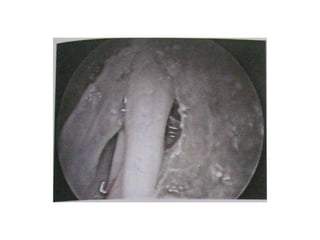

lt ICA SEEN ON LT SIDE.. A HOLE IN THE ARACHNOID..

THE STALK JUST BEHIND IT.. THE DIAPHRAGM SEEN IN

5/6 O CLOCK POSITION..

CSF rhinorrhoea case

Closed with hadad flap